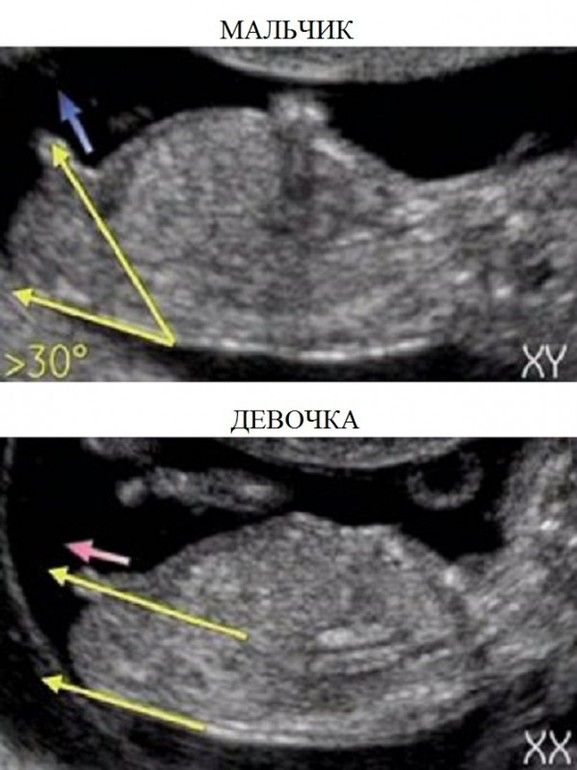

Мальчика вижу

У меня вообще вопрос как там различают пол , я вообще не вижу . Малышок ))